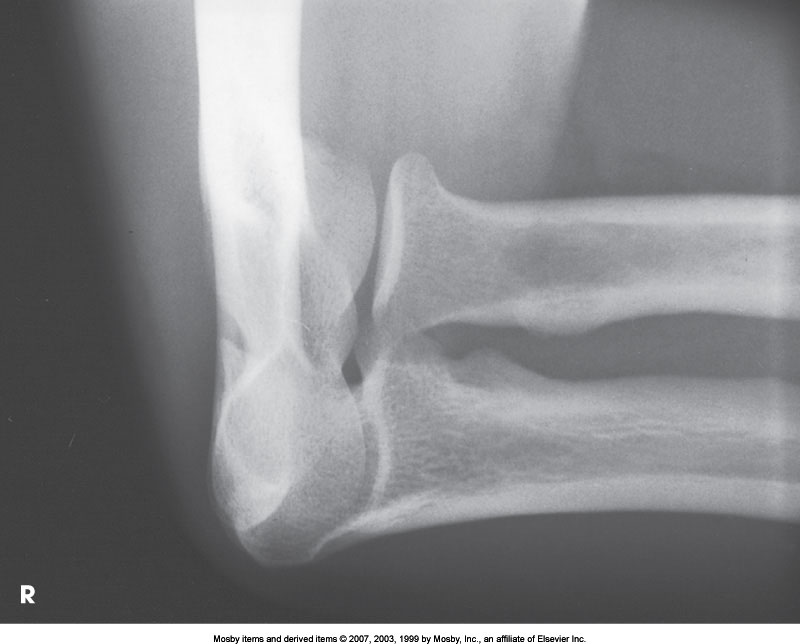

What position is demonstrated?

AP Oblique Elbow (External Rotation)

AP Oblique Elbow (Internal Rotation)